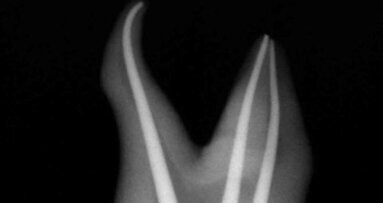

Halfway through the program, participants had the pleasure of experiencing Dr David Clark, who lectured on World Class Obturation for General Dentists. Attendees were taught the risks and benefits of lateral condensation technique versus vertical compaction of heated gutta-percha / resin-based obturation. Dr Clark provided step-by-step instruction on the clinical steps required for plasticized gutta-percha technique utilizing pack down and back-fill techniques with modern equipment including microscopes, ultrasonics and the new Obtura III Max unit.

Next, Dr Garry Bey lectured on Tips, Tricks and Solutions for Endodontic Success. Attendees learned how to reduce separation anxiety; to virtually eliminate the risk of sodium hypochlorite accidents; to achieve a lasting seal with carrier-free obturation and warm vertical compaction; and to practice-build, by keeping the cases they would normally refer out, and develop the confidence to do them well.